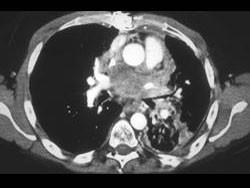

问题 男,45岁,咳嗽,咯血2月余,有20余年吸烟史,请结合影像学检查图,选出最可能的诊断 ( )

选项 A、肺囊肿 B、肺错构瘤 C、小细胞肺癌 D、肺脓肿 E、肺结核

答案 C